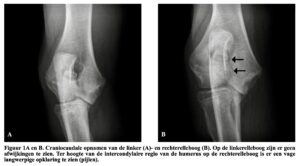

Figuren afkomstig uit ‘Incomplete ossification of the humeral condyle in a young Dogue de Bordeaux’, S.Favril et al. Met toestemming van Professor Van Ryssen Ugent.